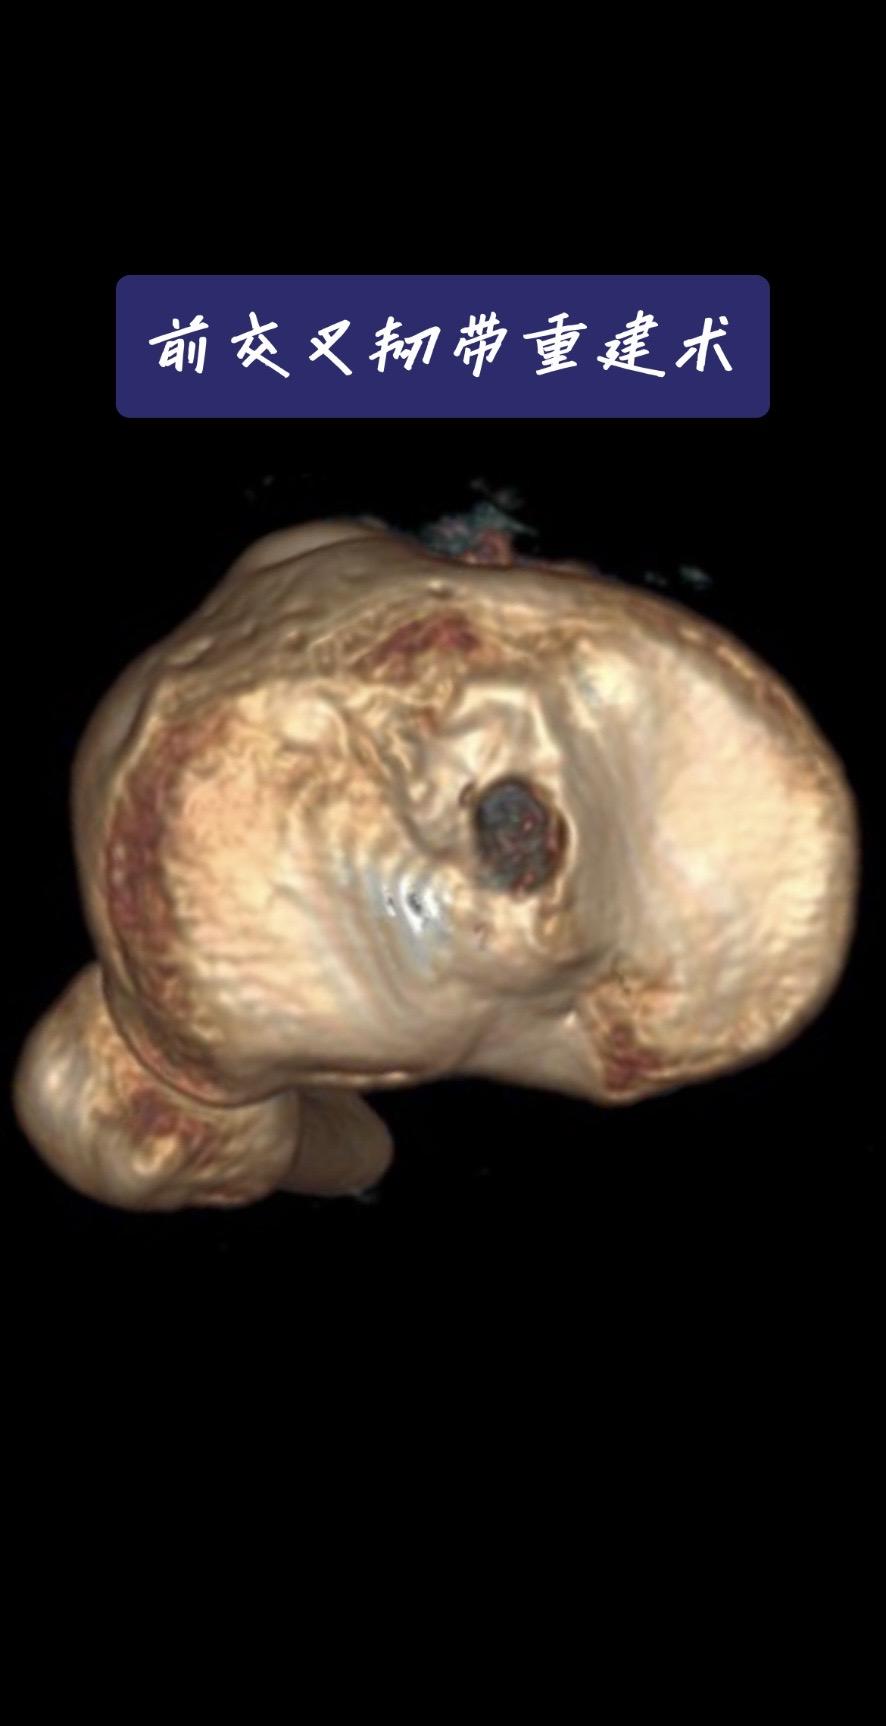

前交叉韧带重建。一台成功的前交叉韧带重建,关键在于“精准”二字。术后CT、MRI复查,就是我们医生的“成绩单”。前交叉韧带重建 运动医学 膝关节术后 骨科医生 医学科普